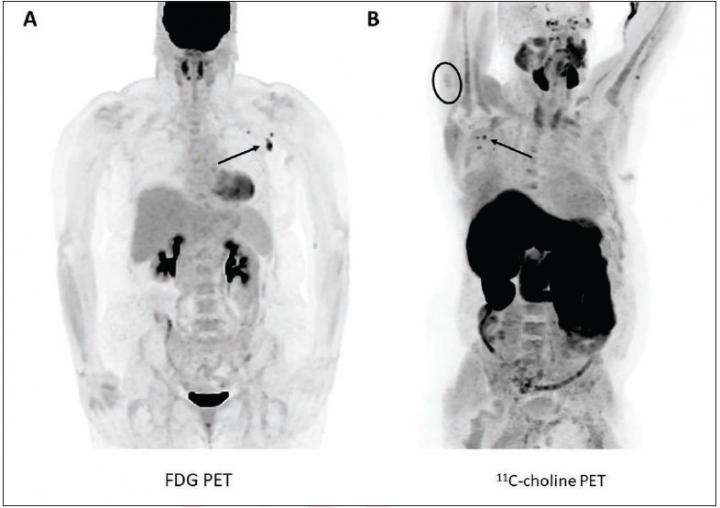

Nodal and deltoid radiotracer uptake on post-COVID-19 vaccination PET

image: (A) 57-year-old woman with right upper arm melanoma who received the first dose of the COVID-19 vaccine (Pfizer-BioNTech) in the left deltoid 15 days prior to FDG PET/CT. FDG uptake is observed within left axillary lymph nodes (arrow, SUVmax = 9.3). (B) 62-year-old man with metastatic prostate carcinoma who received the second dose of COVID-19 vaccine (Pfizer-BioNTech) in the right deltoid 7 days prior to 11C-choline PET/CT. 11C-choline uptake is observed within right axillary lymph nodes (arrows, SUVmax = 3.1) as well as the right deltoid muscle (circle, SUVmax = 1.7).

"We observed positive axillary lymph nodes in 7.4% of FDG and 23.1% of 11C-choline PET examinations performed after COVID-19 vaccination (10.4% of PET examinations) in patients without visible axillary nodal uptake on PET performed before vaccination," Young et al. concluded. Ipsilateral deltoid uptake with a characteristic appearance was observed in 14.5% of examinations, and one patient exhibited extraaxillary lymph node uptake (ipsilateral supraclavicular uptake on FDG PET).